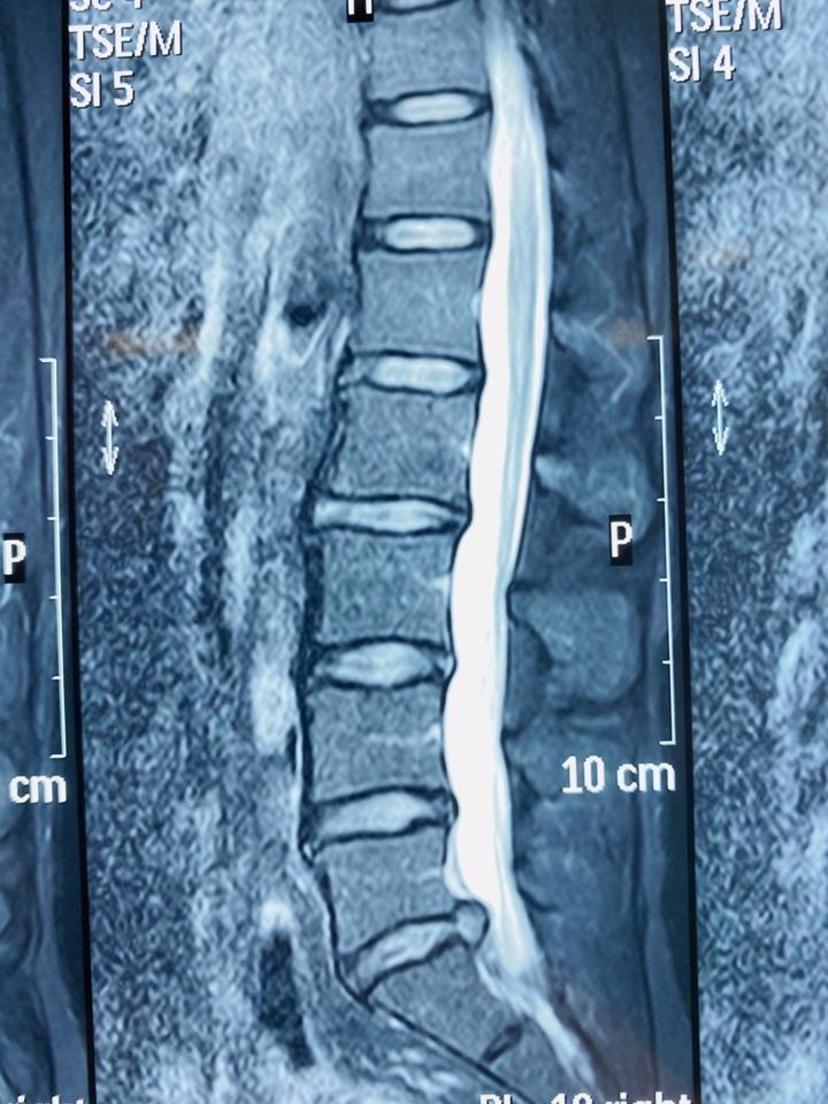

患者腰背痛10年,近半年左下肢疼痛麻木,不能正常行走,生活质量大大降低,经腰椎磁共振检查诊断出腰5-骶1椎间盘巨大突出,左侧神经受压明显,住院后当天采用局部麻醉下,经椎间孔镜技术微创治疗,整个手术过程仅仅半小时,切口0.5cm,完整取出压迫神经的髓核组织,后腰部及下肢不适症状完全消失,术后第二天早上出院,整个住院时间不到24小时!磁共振显示腰5-骶1椎间盘巨大突出,硬膜囊受压严重

磁共振平扫显示左侧神经根严重受压